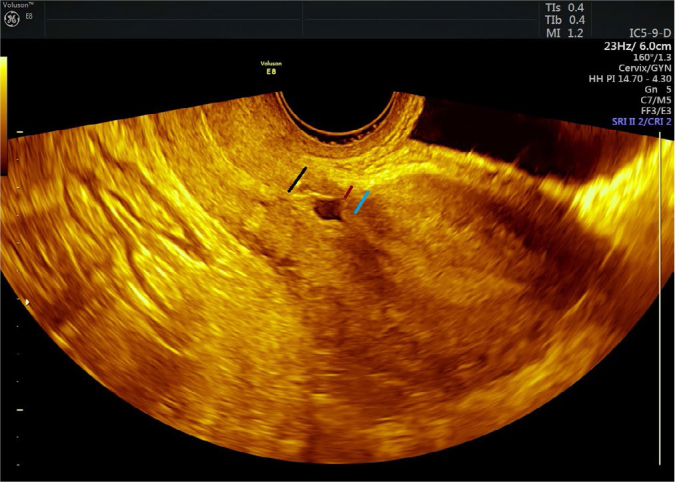

Material and methods: This prospective study included pregnant women diagnosed with diabetes mellitus and healthy control pregnant women. The study group was divided into active labor and pre-active labor based on cervical dilatation, and the diabetic group was categorized into gestational diabetes and preexisting diabetes mellitus. Vaginal ultrasound was performed in the entire study group at six months postpartum, and the location of the cesarean scar was evaluated.

Abstract Image